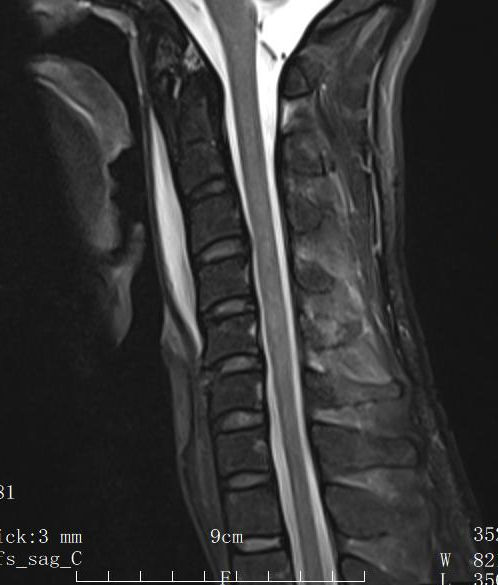

在紧急送至中山市第六人民医院后,脊柱外科二区专家团队经过详细检查,确诊患者为“颈5/6无骨折脱位型脊髓神经损伤”,并伴有颈5/6椎间盘严重损伤。

▲术前MRI

中山市第六人民医院脊柱外科二区程俊杰主任医师解释道:“虽然X光片上看不到典型的骨折或脱位,但瞬间的外力冲击已导致颈椎椎间盘、韧带等稳定结构受损,如同一个‘隐形杀手’,对内部的脊髓神经造成了严重压迫与挫伤。若不及时干预,可能导致患者四肢瘫痪等严重后果。”